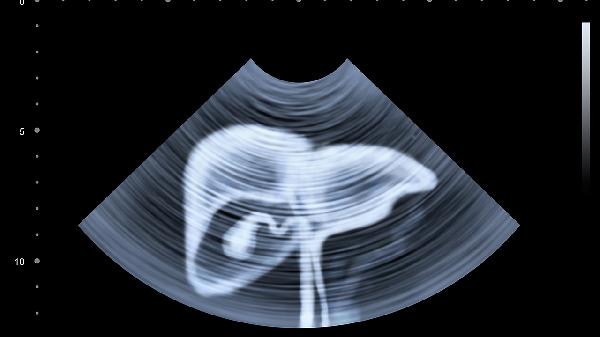

少数情况下,伴随腹痛、背痛或搏动范围扩大的异常跳动需警惕腹主动脉病变。腹主动脉瘤患者可能出现搏动性肿块,瘤体增大可压迫周围器官导致持续疼痛。马方综合征等结缔组织疾病也可能引发血管异常搏动。若跳动频率异常或伴随呕血、休克等症状,需立即就医排除血管破裂风险。

日常应注意避免剧烈运动或突然增加腹压的动作,控制血压和血脂有助于维持血管健康。定期体检时可通过腹部超声筛查血管异常,40岁以上有吸烟史或高血压人群建议每年检查血管弹性。出现搏动强度突然改变或体位无关的持续性跳动时,应及时到血管外科就诊。